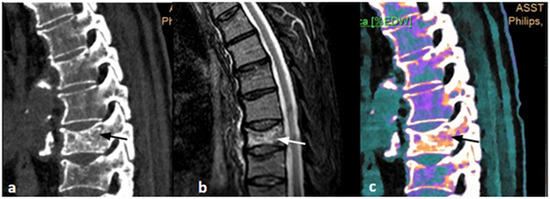

Figure 3. A 55-year-old male, work-related trauma. (a) Sagittal CT image, baseline acquisition of the thoracic spine shows intervertebral disc alteration with cortical irregularities of the opposing endplates (black arrow). (b) Sagittal MRI acquisition with PD/T2 FAT-SAT demonstrates intraspongious edema of the D5 and D6 vertebral bodies, indicating acute interstitial hemorrhage (black arrow). (c) Sagittal DL-SCT image, post-processed with IntelliSpace system, highlights the presence of edema through increased electron density, visualized in orange coloring (black arrow). Color bar legend. White: normal cortical bone; orange: intermediate to high ED; purple: low ED; blue: very low ED, consistent with normal bone marrow composition rich in fat.